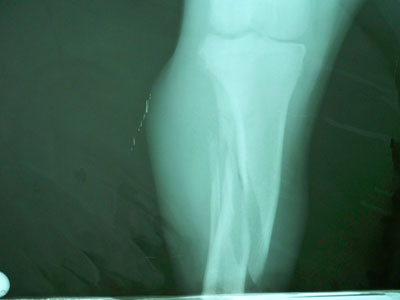

Γιαπωνέζικο mastif 11 μηνών με πρόσφατο λοξό κάταγμα στο άνω / τρίτο της διάφυσης της δεξιάς κνήμης και περόνης.